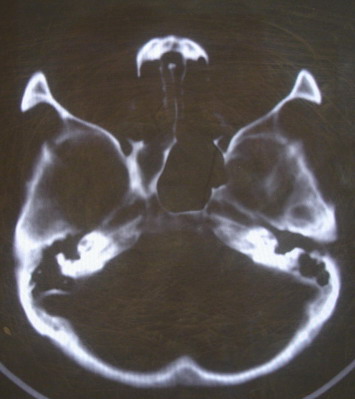

女 63岁 左额部碰伤

现有资料未见骨折表现

左枕部颅缝略增宽并轻度错位,建议结合临床,必要时复查

未见明显骨折

未见异常.

未经高分辩率处理。未见明显异常。

左额部未见明确骨折

左侧颞枕部颅缝分离骨折可疑。建议结合临床,必要时复查。

都错位了,当然是报骨折了。

左侧颞枕部颅缝分离骨折可疑。

结合临床,排除左侧颞枕部颅缝分离骨折可能。